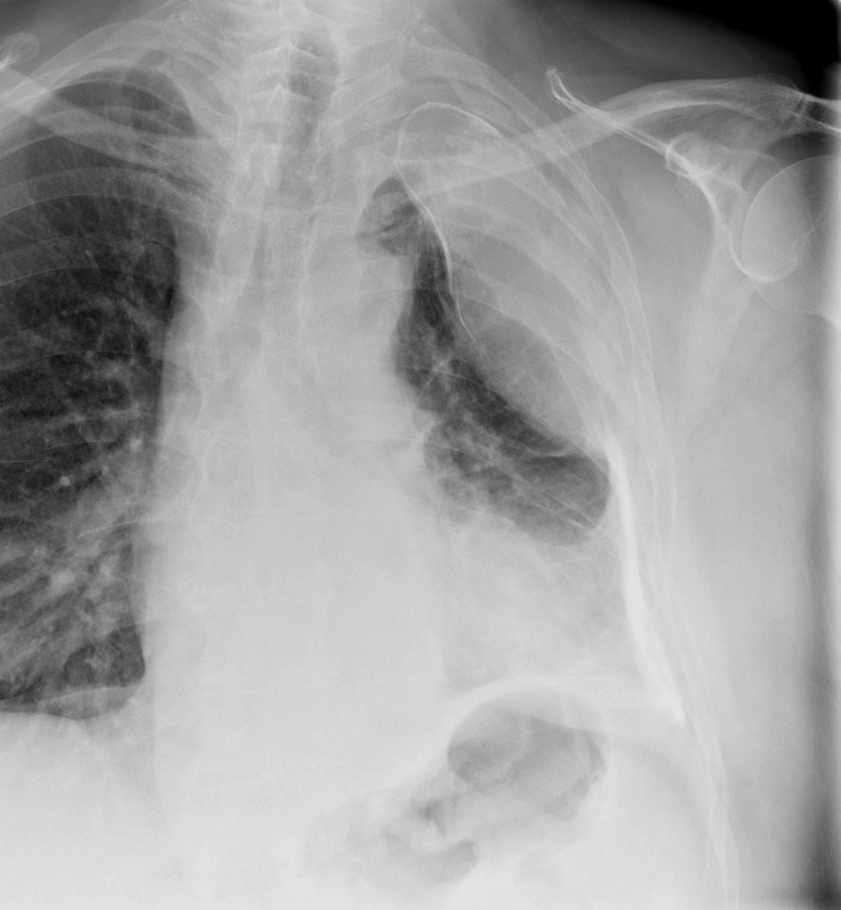

Pleural

calcified emp PA